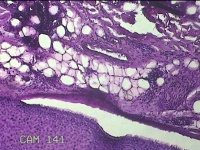

性别

男

年龄

34岁

临床诊断

头部脂肪瘤

一般病史

发现头皮包块2年余。考虑头部脂肪瘤

标本名称

头皮包块

大体所见

灰白粉红色梭形皮肤包块3x2x0.7cm一个,表面糜烂,切面灰白粉红色,质软。